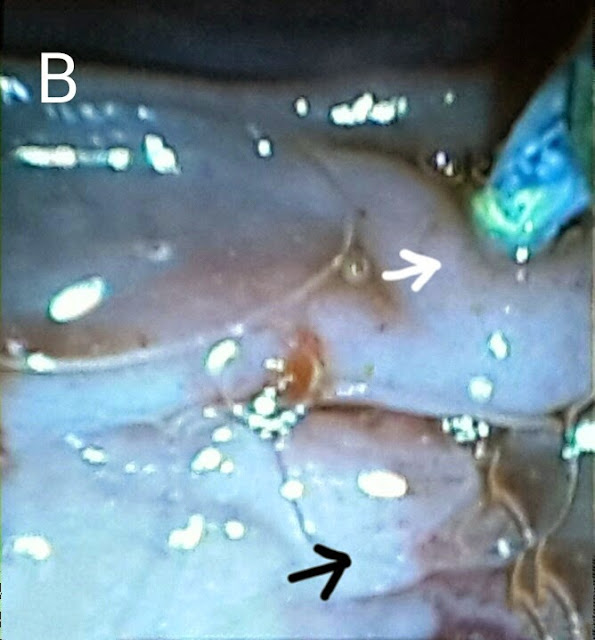

This 50 year old gentleman had come for his 4th follow up procedure after developing jaundice and recurrent fever. We removed his old plastic sent placed during his previous (3rd) ERCP http://ercp365.blogspot.com/2014/09/third-follow-up-ercp-for-post.html using a snare. Contrast injection outlined the anastomotic stricture (A: black arrow). We dilated the stricture using a TTS balloon inflated to 8mm (B: white arrows show the balloon assembly in place at the stricture site with the balloon inflated). A 10 French plastic stent of 12 cm length was placed.